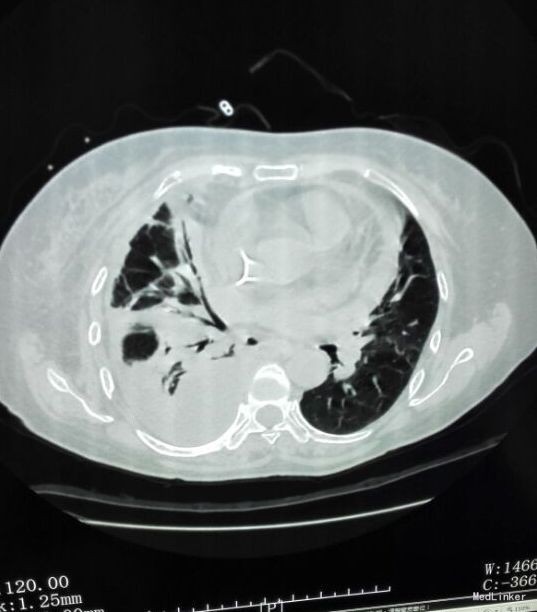

患者入院后予“美洛西林舒巴坦”抗感染,当天晚上出现明显气促,伴右后下背痛,无明显发热,当时复查胸片示: 1、双下肺炎症、双侧胸腔积液,同2015.12.13前片比较,考虑右侧胸腔积液明显增多,部分包裹,建议CT进一步检查。血气分析未见明显异常,2015-12-14 复查急诊血常规:白细胞计数 24.290(10E9/L)↑,淋巴细胞计数 0.750(10E9/L)↓,中性粒细胞比例 0.930↑,血红蛋白浓度 104.000(g/L)↓,中性粒细胞计数 22.590(10E9/L)↑,红细胞计数 3.500(10E12/L)↓,血小板计数 466.000(10E9/L)↑,单核细胞计数 0.920(10E9/L)↑;急诊肾功(三项):尿素氮 8.450(mmol/L)↑;急诊电解质(K/Na/Cl):钠 128.700(mmol/L)↓,氯 87.100(mmol/L)↓; 2015-12-14胸部及上腹部CT平扫+增强示:1、两中下肺多发炎症,部分萎陷。建议治疗后复查。2、双侧胸腔积液(右著);心包少量积液。3、结合病史,右输尿管术改变;右侧双J管置入术后。右肾、输尿管上段扩张、积水,右肾周感染并少许积气;左肾结石。4、脂肪肝。5、胆、脾、胰未见异常。因CT提示肺部大片实变,包裹性积液(量少),考虑重症肺炎可能,于2015-12-14将抗生素升级为“亚胺培南西司他丁 1.0 q8h、万古霉素 50万U q12h、伏立康唑 0.2 q12h”三联,同时予“甲强龙”抗炎等治疗。经治疗,患者气促症状逐渐缓解,咳嗽、咳痰、右后背疼痛好转,无发热,精神、胃纳较前改善。因B超定位下胸水量少,暂未予胸穿。2015-12-17复查胸部+上腹部CT平扫示:1、双中下肺炎炎症较前吸收好转,右侧胸腔积液较前略有减少,左侧胸腔积液现已基本吸收。2、胸、腹主动脉粥样硬化;心包少量积液(大致同前)。纵膈内临界肿大淋巴结。3、右输尿管术改变;右肾、输尿管上段扩张、积水,右肾周慢性感染(原右肾周积气消失);左肾结石。4、轻度脂肪肝。少量腹水。5、胆囊内斑片状高密度影,考虑胆汁淤积。2015-12-19 复查血常规:白细胞计数 18.160(10E9/L)↑,中性粒细胞比例 0.918↑,血红蛋白浓度 105.000(g/L)↓,中性粒细胞计数 16.670(10E9/L)↑,红细胞计数 3.560(10E12/L)↓,血小板计数 396.000(10E9/L)↑,淋巴细胞比例 0.037↓,红细胞压积 0.305↓,单核细胞计数 0.780(10E9/L)↑;降钙素原 2.000(ng/ml)↑;急诊肾功(三项):肌酐 146.000(umol/L)↑,尿素氮 19.580(mmol/L)↑。2015-12-20患者精神较前明显变差,伴纳差、乏力,气促较前加重,2015-12-20再次复查血常规:白细胞计数 33.230(10E9/L)↑,中性粒细胞比例 0.967↑,红细胞计数 3.350(10E12/L)↓,中性粒细胞计数 32.130(10E9/L)↑,血红蛋白浓度 99.000(g/L)↓,单核细胞比例 0.016↓,淋巴细胞比例 0.016↓,红细胞压积 0.293↓;2015-12-20 急诊肾功(三项):肌酐 125.000(umol/L)↑,尿素氮 15.960(mmol/L)↑;降钙素原 0.836(ng/ml)↑;复查胸片示:1、同2015.12.17胸部CT比较,考虑右侧胸腔积液较前有所增多,大部分为包裹性积液,新发左侧胸腔少量积液;右肺情况显示不清,左下肺炎症。2、心影增大,结合CT考虑心包积液;主动脉粥样硬化。遂行胸腔穿刺术,抽出400ml黄白色脓性胸水,胸水常规:PH6.0,WBC54600*10E6/l,中性粒0.97,胸水生化:乳酸脱氢酶 2221.000(U/L);葡萄糖 1.180(mmol/l),总蛋白 24.000(g/l),腺苷脱氨酶 154.000(U/L),氯 106.800(mmol/L)。符合脓胸改变,予右侧胸负压腔闭式引流,同时予“庆大霉素16万u”冲洗,将抗生素降级为莫西沙星片口服,患者症状明显好转,12.24复查胸片及CT胸腔积液及肺炎均较前明显好转。